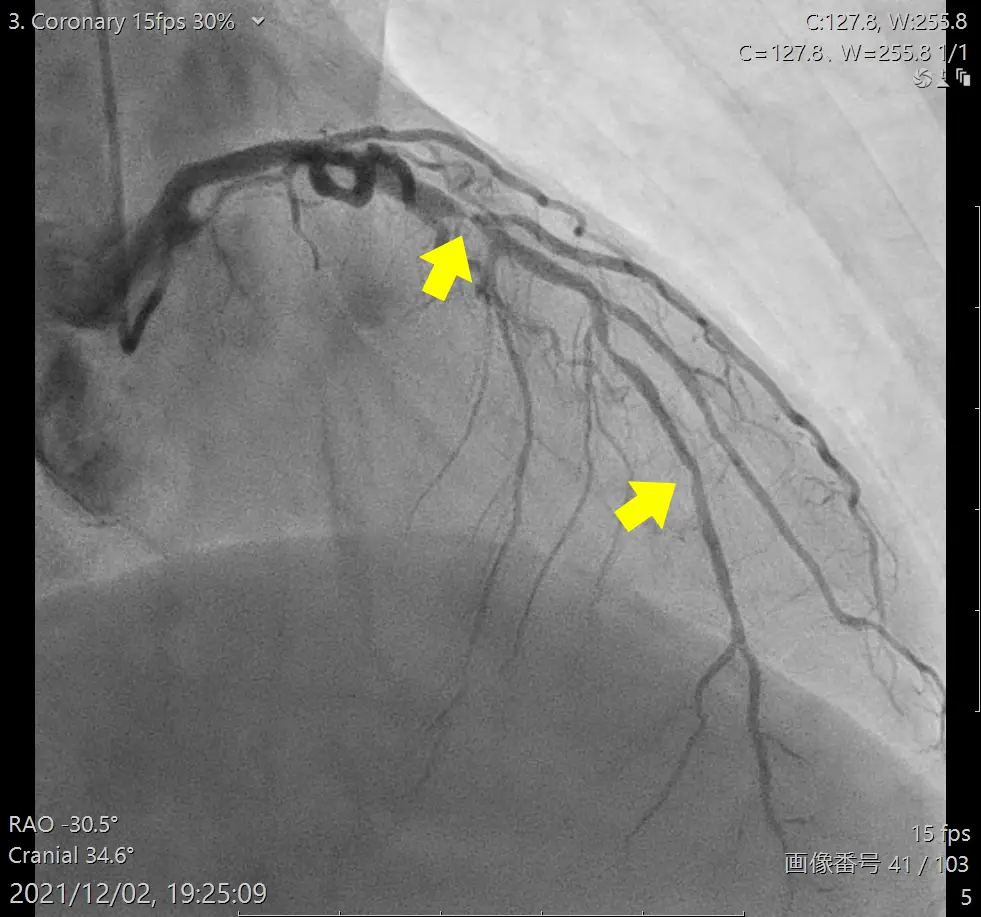

- カテーテル造影検査